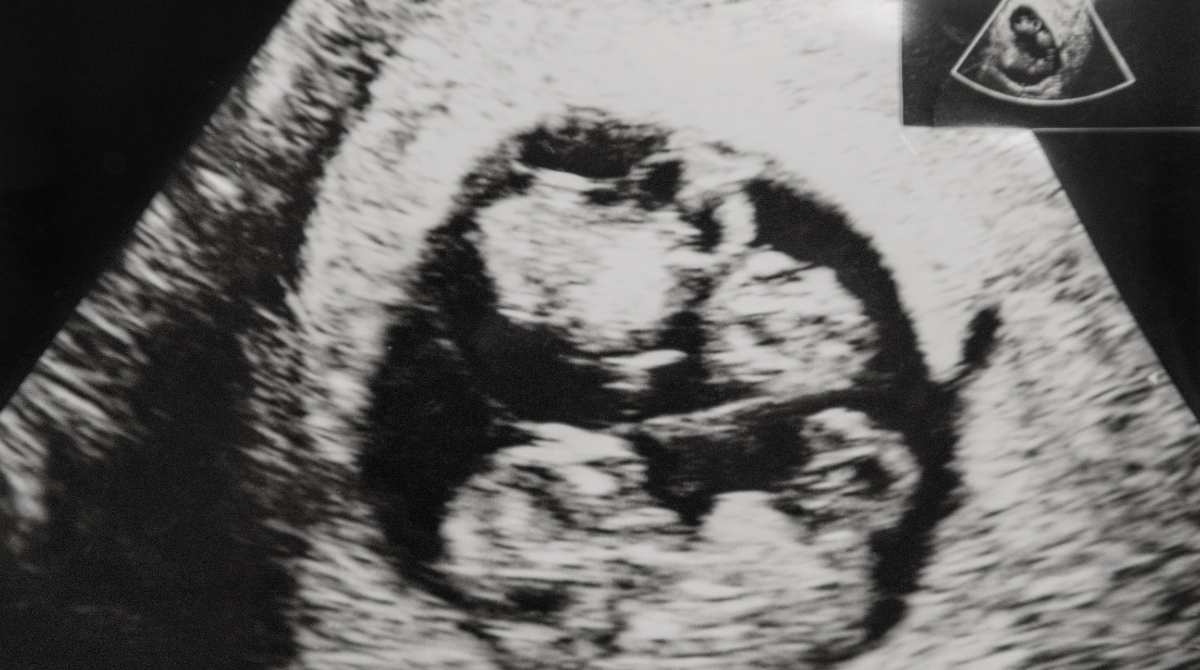

Entah apakah saat itu Chelsea sedang hamil atau sekadar memeriksa sel telurnya. Namun dalam video tersebut Glenn dan dokter membicarakan kemungkinan Chelsea mengandung anak kembar. Tidak tanggung-tanggung, 4 anak sekaligus.

“Ada berapa, tuh?” tanya Glenn kepada dokter.

“Nih, ada 11,” jawab dokter kandungannya. “Yang ukurannya 5-11 mm ada empat, yang 2-5 mm (ada) tujuh,” tambah si dokter lagi.

Lalu Glenn pun merespon “Bisa kembar 4, dong?”